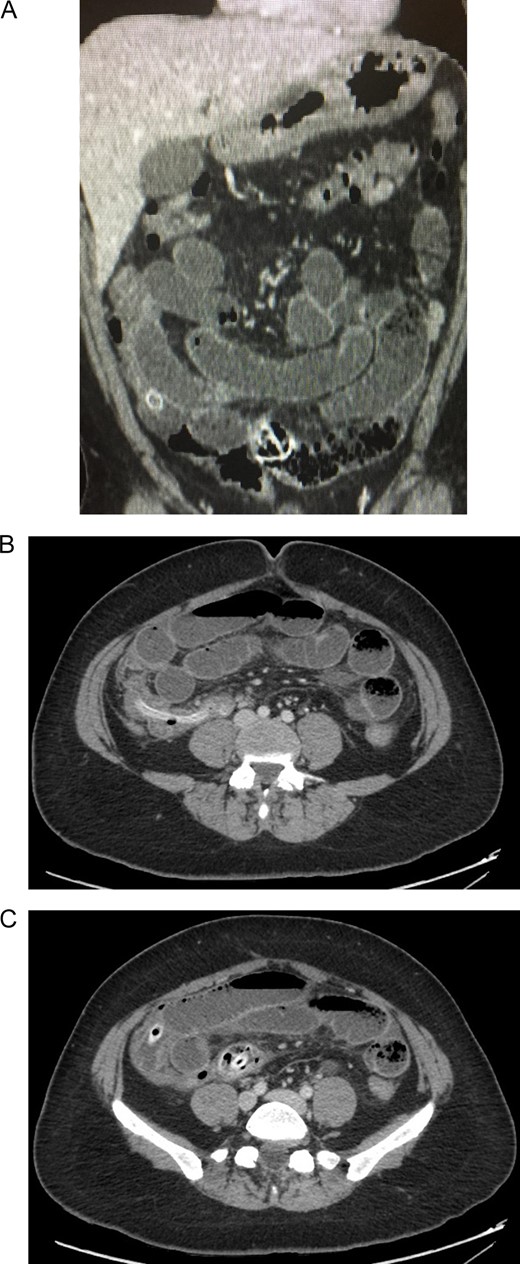

The patient is a 38-year-old female with past medical history of obesity, for which she was treated with a saline-filled intragastric balloon 5 months prior. The patient’s initial body mass index (BMI) was 33.18, and during this time, she had lost 12 kg of weight, reaching a BMI of 31.85. She presented to the emergency room with a 4-day history of lower abdominal pain, nausea and severe vomiting. She also reported that she was unable to pass gas or stool. On clinical examination she was found to be dehydrated and tachycardic, her abdomen was distended and she had generalized abdominal tenderness. On auscultation, tinkling bowel sounds associated with gurgles and rushes were identified. After adequate reanimation, a CBC (complete blood count) revealed leukocytosis and neutrophilia, and a contrast-enhanced abdominal computed tomography (CT) unveiled a 10 × 2 × 1.5 cm3 metallic foreign body located in the lumen of the terminal ileum and the cecum. The intestinal loops proximal to the ileum were dilated, showing clear signs of bowel obstruction proximal to the aforementioned foreign body (Fig. 1).

(A) Contrast-enhanced abdominal CT: intestinal loops are dilated. (B) Contrast-enhanced abdominal CT: a metallic foreign body is seen in the ileum. (C) Contrast-enhanced abdominal CT: showing clear signs of bowel obstruction.